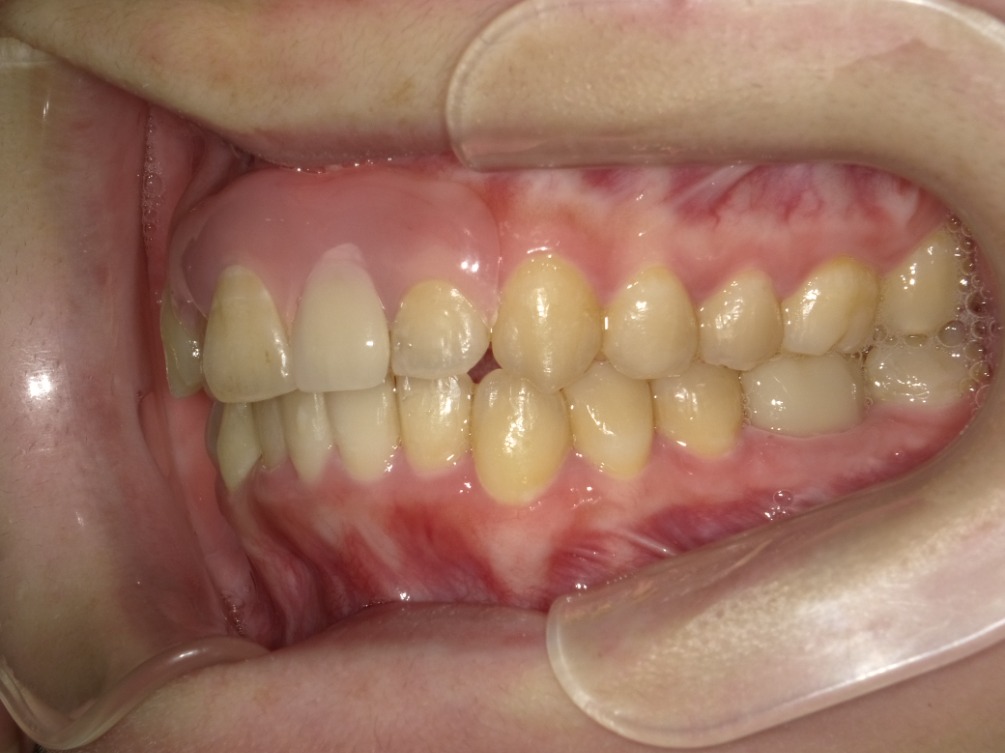

右横

左横

| 治療内容 | インビザライン 全顎〈抜歯あり〉 |

| 治療詳細 | 叢生や交叉咬合を整えるために、歯の表面にアタッチメント(白い突起)をつけ、IPR(歯と歯の間を削る)を行いました。 また、顎間ゴムと呼ばれる引っ掛けるゴムの補助装置も用いて治療を行いました。 抜歯を1本して治療を行いました。該当部分は義歯を使用しています。 |

| 患者情報 | 20代 女性 デンタルモニタリング使用 |

| 主訴 | 歯のがたつき 一部分だけかみ合わせが反対 |